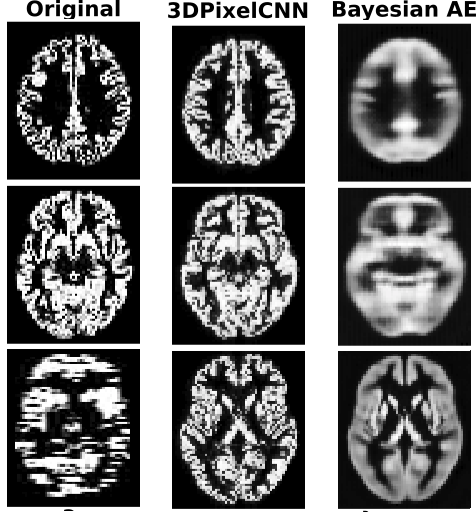

Figure 2 shows a representative selection of reconstructions of GM volumes and unsupervised lesion masks produced using τ(xi)𝜏subscript𝑥𝑖\tau(x_{i}). Notice on the MRI reconstruction, when the original image is corrupted, the 3DPixelCNN model acts as a super resolution mechanism, further showing the model has learnt p(𝒙)𝑝𝒙p(\boldsymbol{x}) and is not simply memorising the training set.

(b) MRI bayesian reconstructions

Figure 2: (a): From left to right: 1) The slice through the axial plane with the greatest area of lesion, 2) The stroke label map , 3) τ(xi)𝜏subscript𝑥𝑖\tau(x_{i}) 4) |xiAE(xi)|subscript𝑥𝑖𝐴𝐸subscript𝑥𝑖|x_{i}-AE(x_{i})| 5) τ(𝝈)𝜏𝝈\tau(\boldsymbol{\sigma}). 𝝈𝝈\boldsymbol{\sigma} helps capture the tighest bound on the lesion (b) Axial slices of 1) The original volume, 2) The 3DPixelCNN reconstruction and 3) The Bayesian AE reconstruction (On the last volume there was a capture problem and we use it to test 3DPixelCNN’s ability to super resolve)